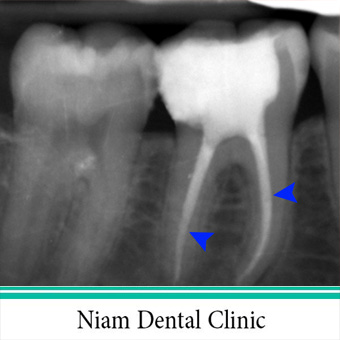

در یک تصویر رادیوگرافی ، سیلر و گوتاپرکا که داخل ریشه قرار گرفته به صورت خطوط مخروطی سفید رنگ داخل ریشه کاملا قابل مشاهده اند.